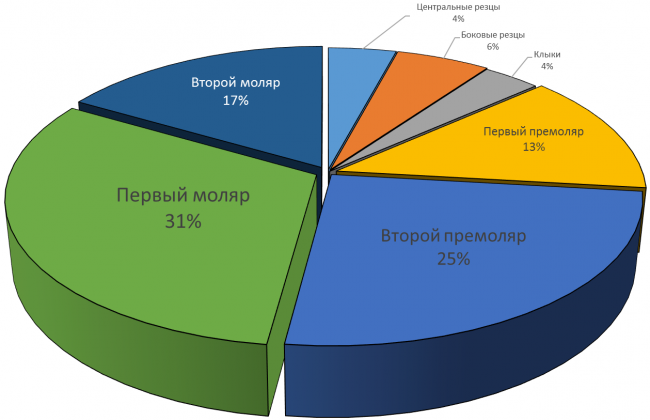

Так ли это на самом деле? Я тут проанализировал собственные данные за 2013 год (статистику 2014 года еще не считал). Главный вопрос, который я перед собой поставил, звучит как:

В КАКИЕ ОБЛАСТИ ПРИХОДИТСЯ СТАВИТЬ ИМПЛАНТЫ ЧАЩЕ ВСЕГО?

Вот 630 одиночных имплантов (не являющиeся опорами мостовидных или иных конструкций), установленных за 2013 год.

Что показывают эти диаграммы?

А показывают они то, что чаще всего приходится имплантировать (в т. ч. немедленно) зубы в боковом участке челюсти: от пятерки до семерки это суммарно около 83% на верхней и 84% на нижней челюсти. Доля зубов фронтальной группы (резцы, клыки, первые премоляры) не очень велика — почти 27% на верхней и менее 16% на нижней челюсти.

Это легко объяснить — утрата или повреждение зуба в зоне улыбки влечет за собой эстетический дефект, поэтому люди изо всех сил стараются их сохранить. К тому же, нагрузка на эти зубы меньше, их легче чистить, а любые, даже самые минимальные их повреждения легко заметить.

Чего не скажешь о больших коренных зубах. Некоторые пациенты на предложение имплантировать давно отсутствующую шестерку задают вопрос: «А зачем? Его же не видно!», не понимая важной функциональной роли боковых зубов.